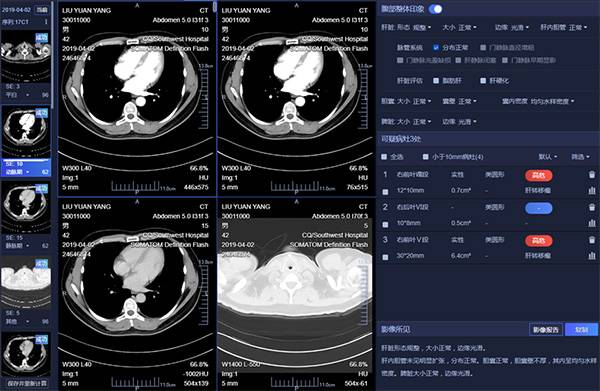

影像智能判读:对肺结节、血管、乳腺钼靶、骨龄等多类型影像进行临床医学判读,提示病灶位置、病灶类型、病灶性状等信息,自动化生成解读报告,帮助临床提高病灶定性解读能力、病灶量化分析能力。可对同一个患者的多次同类型检查进行病灶配准,对病灶变化进行信息提取,也可通过临床医生自建的模型进行影像数据判读,如图5所示。

图5 肝脏病灶识别诊断图